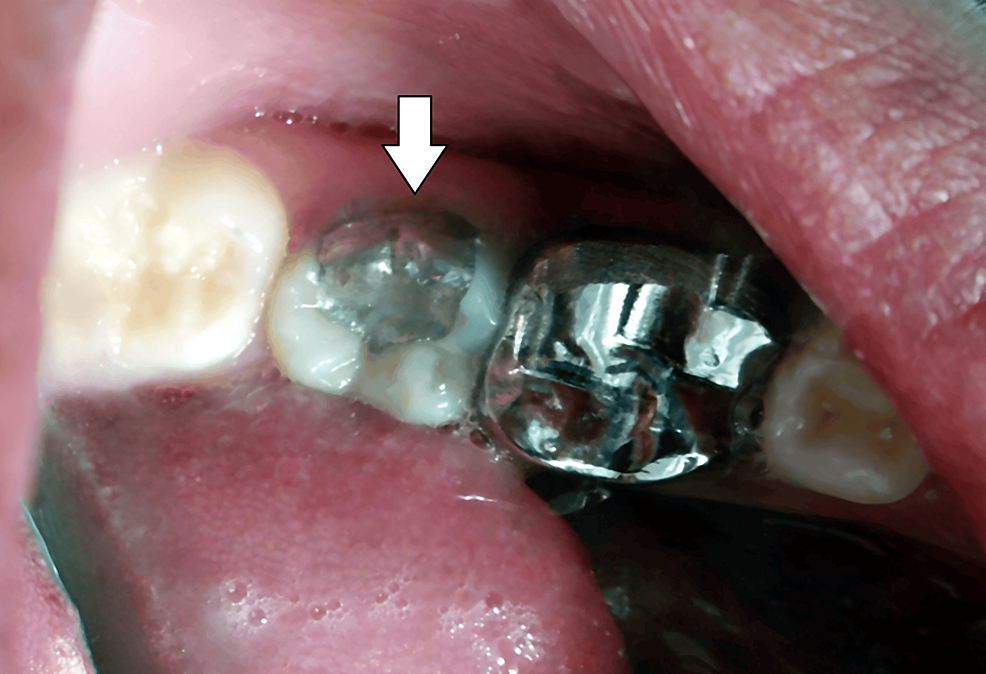

From www.cureus.com

PinRetained Amalgam An Intricate Restorative Case Study Cureus Pin Retained Amalgam — a pin retained restoration is an intricate restoration involving the insertion of one or more pins into the dentin to provide. a pin retained amalgam restoration may be defined as a type of complex amalgam restoration requiring the placement of one. the authors compared the clinical performance of complex amalgam restorations, replacing at. a pin. Pin Retained Amalgam.